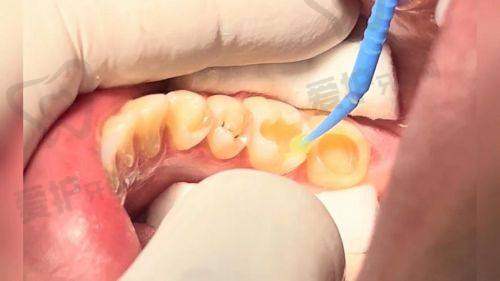

3M树脂250使用的是微米级复合树脂,其填料颗粒约40nm。这种材料是比较早的复合树脂类型。而3M树脂350采用的是纳米级树脂,填料颗粒约20nm。纳米级树脂的优势在于其材料更加细腻,这使得它在抛光后能呈现出更好的成效。相比之下,3m250的材料细腻程度不如350,在一些对表面光滑度和美观度要求较高的情况下,350会更具优势。

硬度方面,3m250的硬度相对较低,而3m350硬度较高。这意味着3m350能更好地承受咀嚼压力。在日常生活中,我们的牙齿需要不断咀嚼食物,承受各种压力。如果补牙材料硬度不够,就容易出现磨损甚至损坏的情况。3m350的高硬度使其更适合用于需要承受较大咀嚼力的区域,比如后牙。

耐磨性上,3m250的耐磨度较弱,长期使用后可能会出现色素沉积或颜色变化,边缘着色的概率也相对较高。而3m350的耐磨性更优,能够在较长时间内保持良好的状态,减少因磨损导致的问题,也能更好地维持牙齿的美观。

美观度是特别多人在补牙时非常关注的一点。3m350在这方面表现出色,它的色泽更接近自然牙,并且提供四大色系36种颜色选择。患者可以根据自己牙齿的实际颜色选择更匹配的材料,从而达到几乎与自然牙无异的成效。而3m250的色泽较暗沉,颜色匹配范围有限,在美观度上稍逊一筹。对于前牙修复,美观度尤为重要,因为前牙直接影响到我们的面部外观和笑容。在这种情况下,3m350可能是更好的选择。

3m250适用于前牙小范围缺损或浅龋修复,它注重经济性。对于一些较小的牙齿问题,使用3m250既能解决问题,又能控制成本。而3m350适用于后牙大缺损或深龋修复,尤其适用于需要承受咀嚼压力的区域,它兼顾了美观与耐用性。后牙在咀嚼过程中承担着重要的任务,需要更坚固、耐磨的材料,3m350正好满足了这些需求。